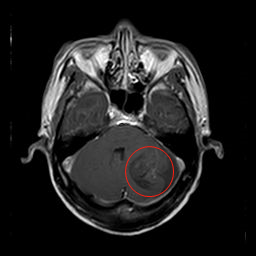

术后头部MR,左侧小脑半球内囊虫病灶已切除。

术前头部MR,左侧小脑半球内一较大的囊性占位,压迫小脑、脑干,为囊虫病变。